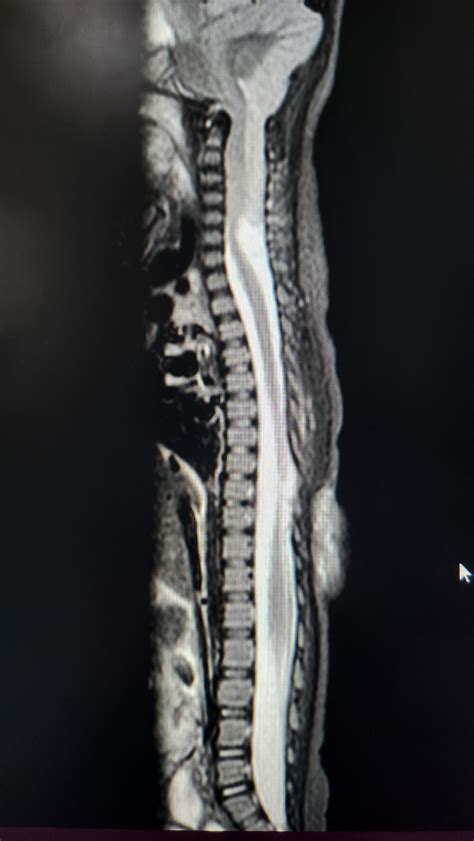

Diagnosing Chiari Type 2 requires advanced medical imaging to visualize the soft tissues of the brain and the integrity of the spinal canal. Because the condition is often identified at birth due to the presence of spina bifida, screening usually begins in the neonatal period.

Diagnostic Tool Purpose

MRI (Magnetic Resonance Imaging) Provides detailed images of the cerebellum, brainstem, and spinal cord to assess the degree of herniation.

💡 Note: MRI remains the gold standard for diagnosing Chiari Type 2, as it provides the necessary contrast to distinguish between nervous tissue and surrounding fluid, allowing neurosurgeons to plan surgical interventions with precision.